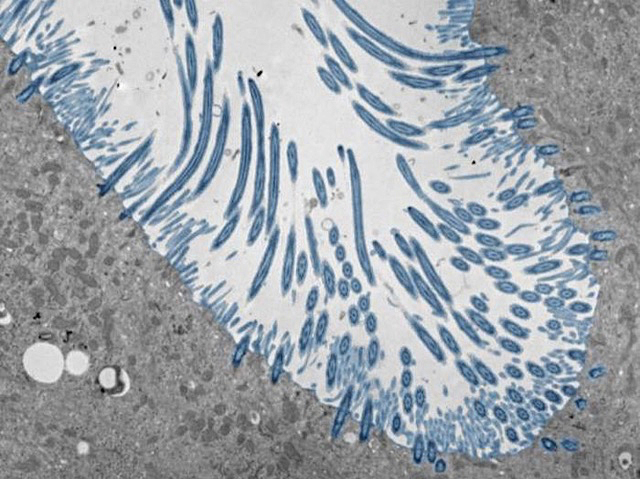

Refredar-se pot provocar quasi cap símptoma en algunes persones, mentre que en altres pot causar una malaltia respiratòria greu. Per a investigar com es generen resultats tan diferents, els científics han estudiat la resposta a la infecció en organoides d’epiteli nasal humà (a la imatge): un conjunt de tipus cel·lulars derivats de cèl·lules mare nasals, que inclouen cèl·lules productores de mucositat i cèl·lules amb cilis (de color blau). Utilitzant rinovirus, la causa més freqüent dels refredats, els investigadors van observar que, quan els organoides produïen, de manera ràpida i robusta, la citocina interferó, limitaven eficaçment la replicació i la propagació del virus. En canvi, una producció deficient d’interferó, o una càrrega viral elevada, feia que les cèl·lules produïren altres citocines proinflamatòries i grans quantitats de moc. El treball mostra com la resposta de l’hoste, més que el virus en si, pot influir en la progressió de la malaltia, i assenyala possibles vies i citocines que podrien ser objecte de teràpies per a afavorir una resposta antiviral saludable.